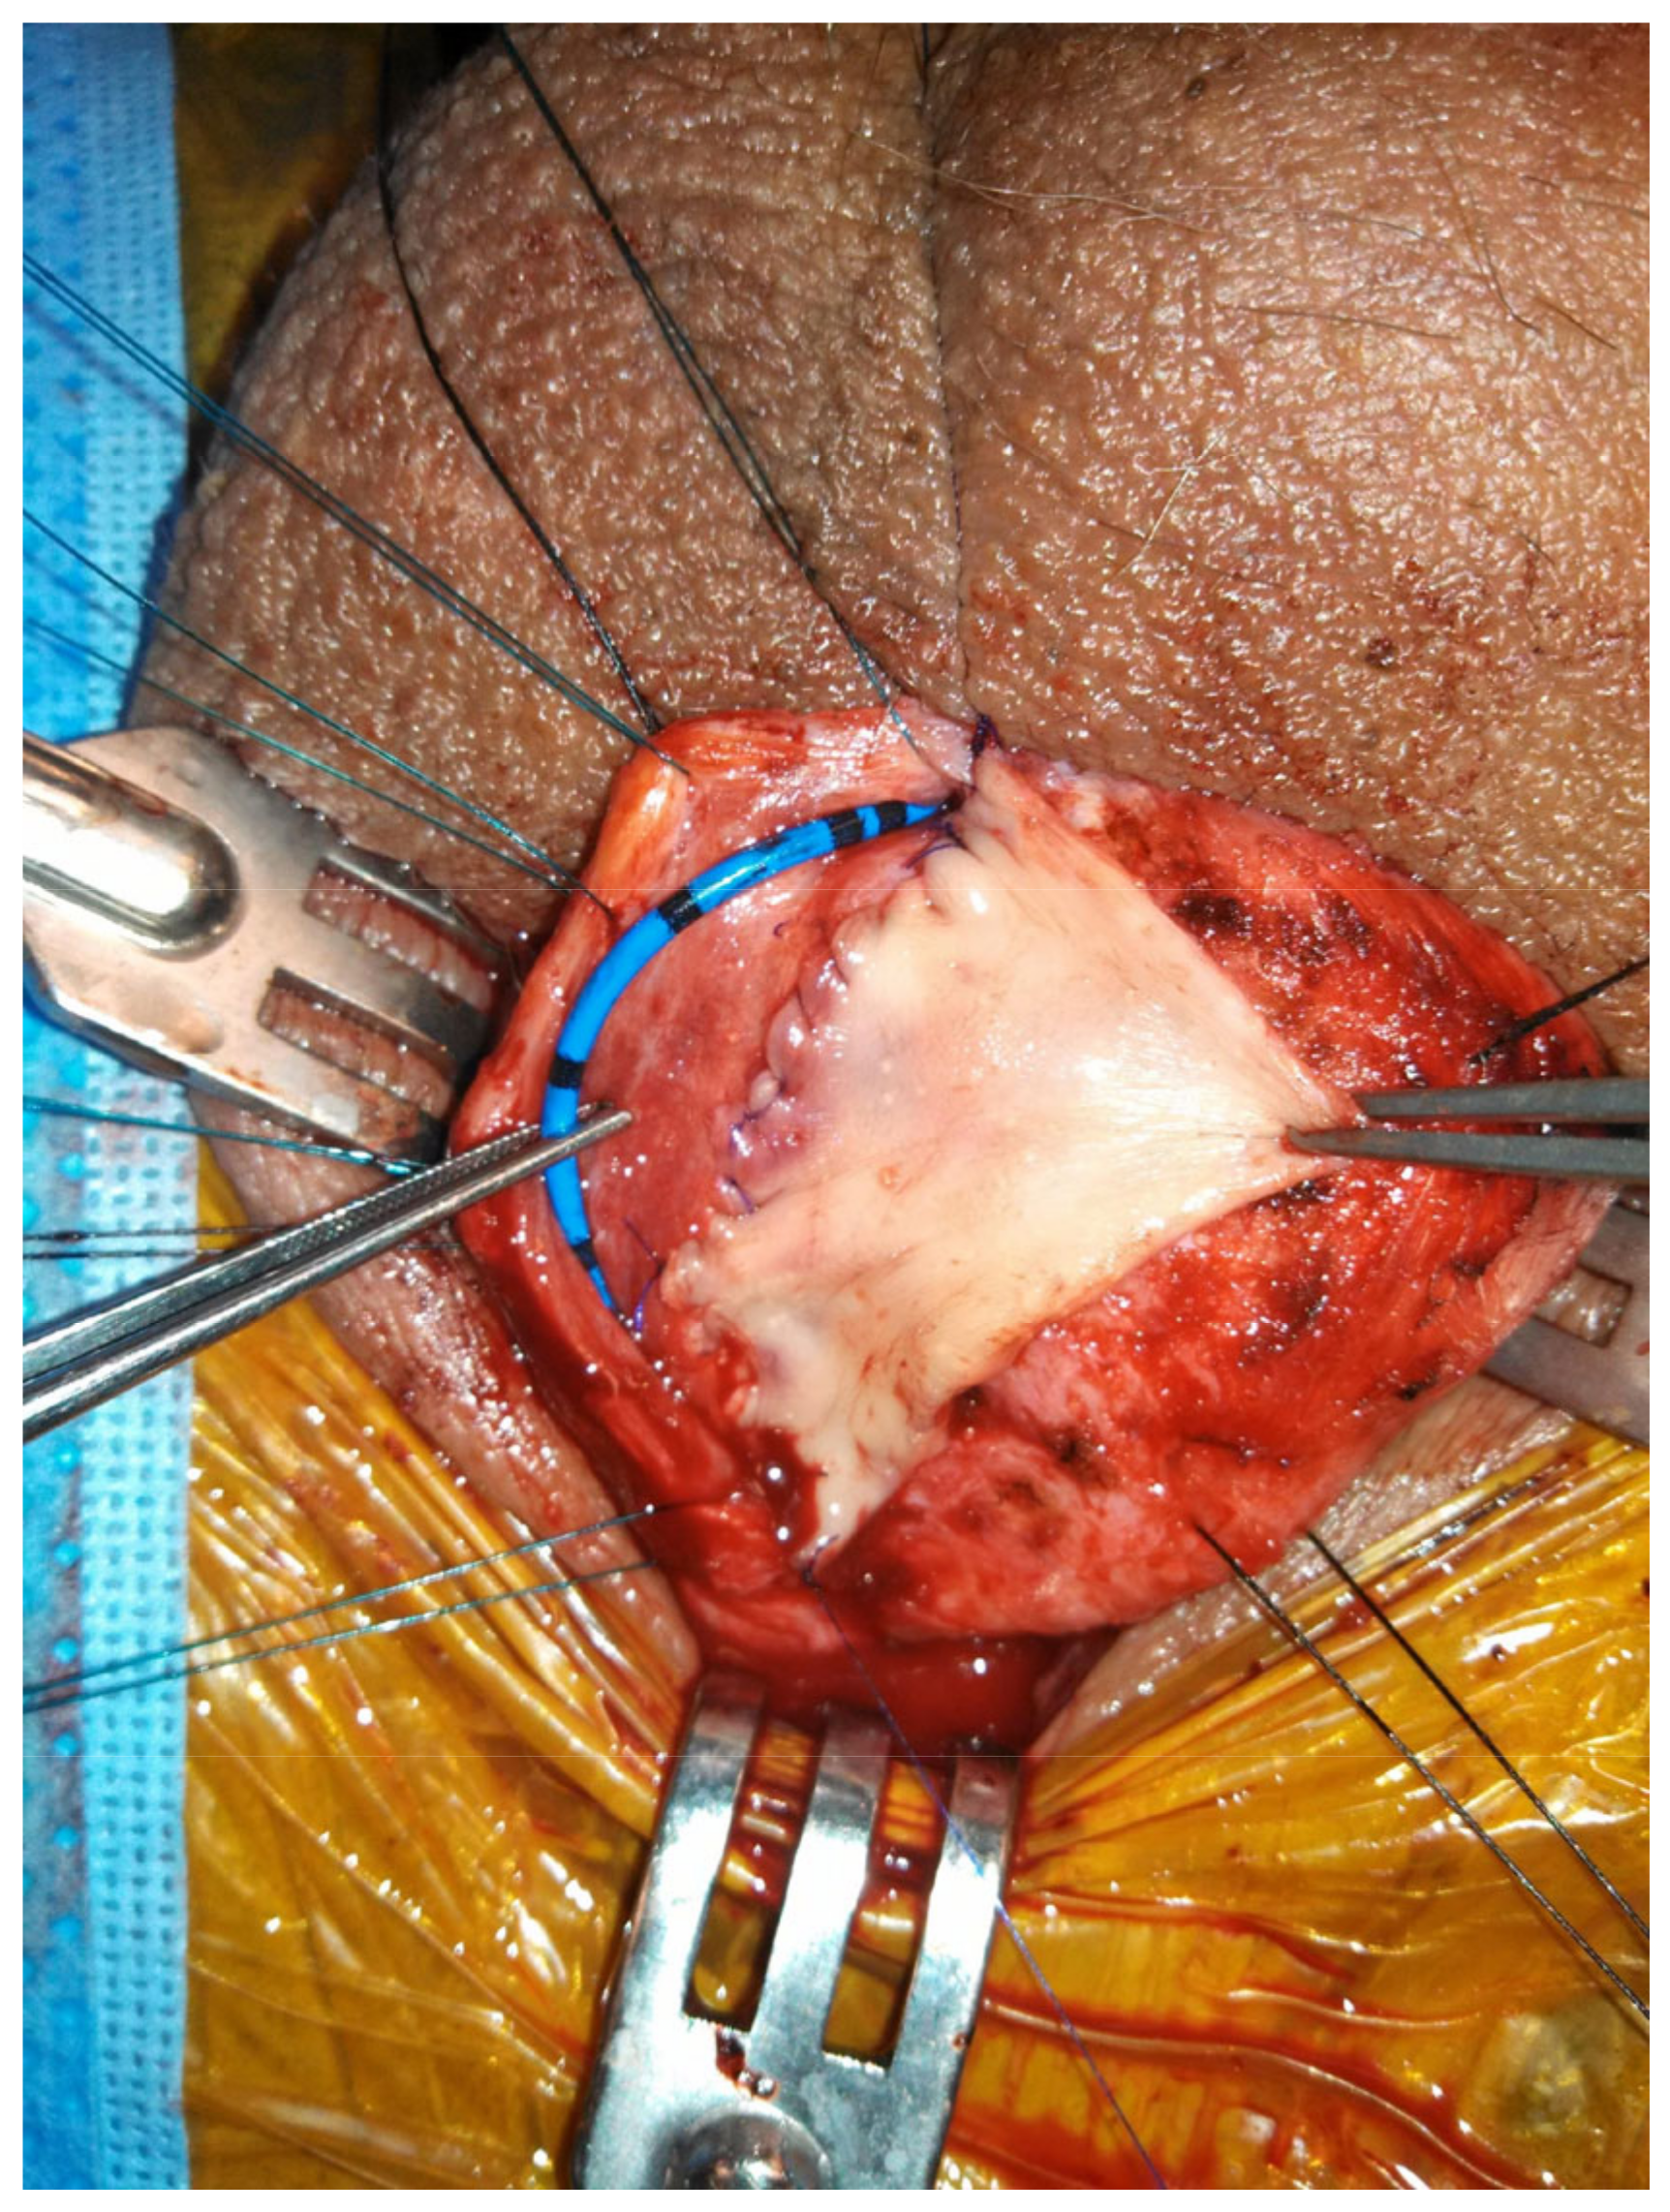

Figure 4. Double graft technique, dorsal approach: (a) the urethra is mobilized off the corpora and the dorsal surface is opened. An incision made in the ventral mucosa; (b) a buccal graft is sutured in the ventral defect; (c) the dorsal urethrotomy is closed with the aid of a second buccal mucosa graft. The urethra is tacked back into position.

Another option when presented with a long (>2 cm) narrow (<4 Fr) stricture is two-sided (dorsal and ventral) grafting technique. The first iteration described by Palminteri in 2008 was performed by making a ventral urethrotomy through which the dorsal urethra is incised to expose tunica albuginea. A dorsal inlay BMG is then placed, followed by a ventral onlay (Figure 3) [31]. Similarly, a dorsal urethrotomy is made through which the ventral urethral mucosa is incised, and a BMG may be inlayed followed by a dorsal onlay (Figure 4). This has the proposed benefit of minimizing trauma to the thicker ventral spongiosum and providing a backing for the ventral graft [32].